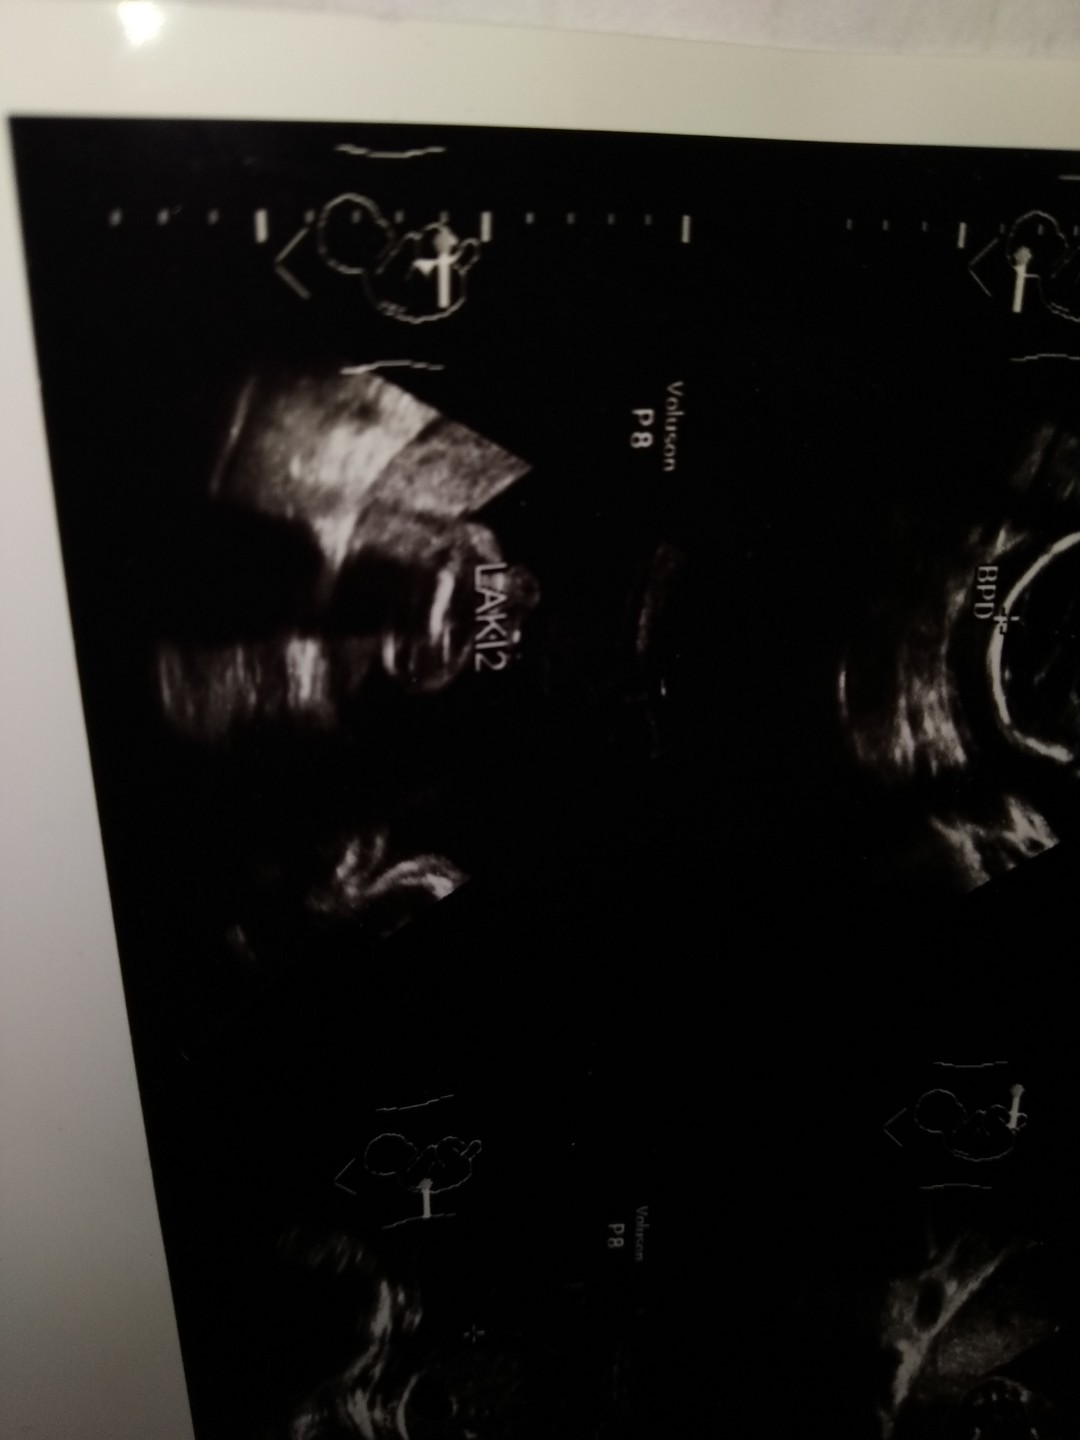

Baby Boy Or Baby Girl

Bun ak mau tanya ni ada ga usg baby girl atau baby boy Nya share Donk bun pengen liat..? Ak jga mau Mtk pendapat usg ku ini baby boy atau girl ya

kayaknya girl bun. gak liat ada monas2nya😂

Udh bun.. Girl katya hehe

Udh bun..... Udh ditanya Girl katya heheh